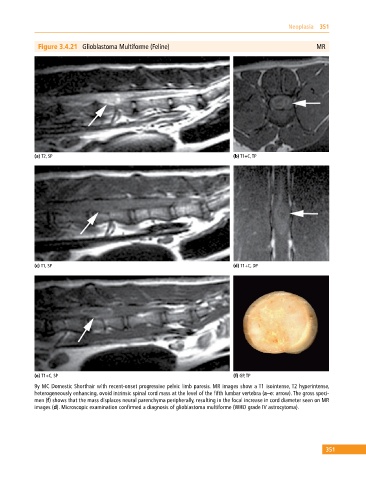

Figure 3.4.21 Glioblastoma Multiforme (Feline) MR

(a) T2, SP (b) T1+C, TP

(c) T1, SP (d) T1+C, DP

(e) T1+C, SP (f) GP, TP

9y MC Domestic Shorthair with recent‐onset progressive pelvic limb paresis. MR images show a T1 isointense, T2 hyperintense,

heterogeneously enhancing, ovoid intrinsic spinal cord mass at the level of the fifth lumbar vertebra (a–e: arrow). The gross speci

men (f) shows that the mass displaces neural parenchyma peripherally, resulting in the focal increase in cord diameter seen on MR

images (d). Microscopic examination confirmed a diagnosis of glioblastoma multiforme (WHO grade IV astrocytoma).